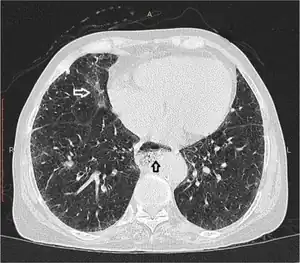

| Esophageal dysmotility black arrow | |